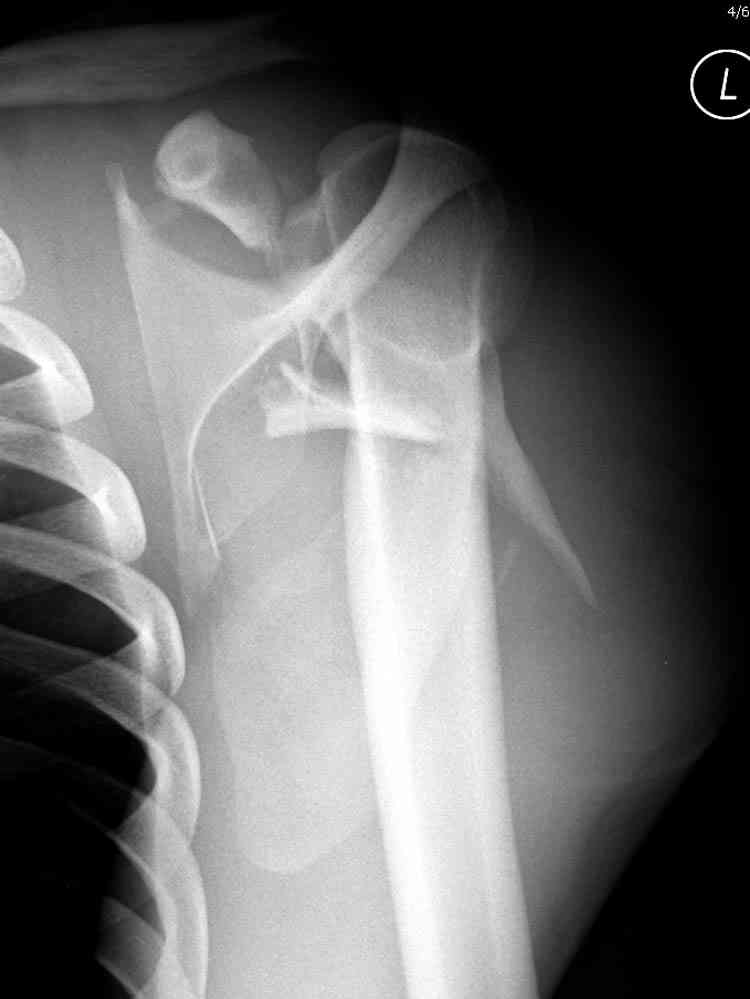

дравствуйте, коллеги. Мужчина 24 лет. Сегодня был прооперирован по Сушко-Илизарову (давно порывался, наконец-то руки дошли :)) На снимке перелом угла лопатки. Довольно крупный размер осколка. Следует ли оперировать такой перелом?Если есть резон оперативного лечения, то каким образом? (рекон. пластина, закрыто пришпилить спицами, винтами). ЭОПа в наличии нет. В области лопатки массивный отек мягких тканей. С уважением, Заднепровский Никита Николаевич

Никита, поздравляю с хорошей репозицией перелома

ключицы.

На какой срок решили оставить в аппарате, и что за аппарат? Разве аппарат Сушко не цилиндрический с движущимися пазами?

Если у вас имеется доказательство, что перелом лопатки изолированный, тогда нет необходимости операции, потому что стабильные изолированные переломы лопатки срастаются хорошо из-за хорошего кровоснабжения.

При отсутствии соединения верхнего пояса с телом из-за перелома ключицы и шейки лопатки имеется состояние "floating shoulder", как в аналогии повреждения около коленного сустава "floating knee" при переломах костей выше и ниже коленного сустава.

В таких случаях, когда нет больших смещений на стороне суставной поверхности, и нет необходимости операции на лопатке, тогда ограничиваются фиксацией только ключицы, то есть фиксируется верхняя конечность к туловищу через ключицу...

Также показания к оперативному вмещательству на лопатке появляются, когда смещения суставной поверхности медиально 9 и более мм и при угловом смещении суставной поверхности 40 и более градусов.

В 1993 Goss описал верхне плечевой поддерживающий комплекс (SSSC-superior shoulder suspensory complex), костно-связочное кольцо из акромиона, коракоида, ключицы и гленоида. Повреждения двух или более элементов из перечисленных доказывают наличие флотирования, и рекомендуется операция.

Посмотрел пациента под рентгеноскопом, определяется изолированный перелом верхнего медиального угла лопатки. Вопрос об операции отпал. Больной машет крылом как пропеллером, пришлось ограничить активность дисциплинирующей "косынкой" ... :))) Отек мягких тканей в области